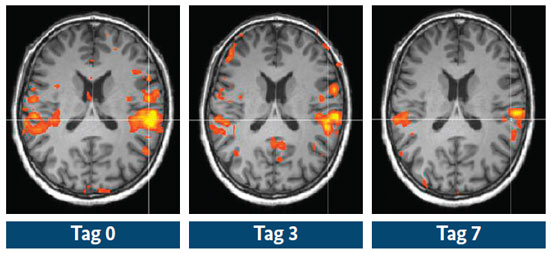

Die Behandlung mit TNF-alpha-Blockern hemmt rasch die neuronale Aktivität im Gehirn der Patienten, hier im fMRT farbig dargestellt, und steigert so ihr Wohlbefinden noch bevor die Entzündung abgeklungen ist.

Der Blick in das Gehirn zeigte, dass bereits einen Tag nach Beginn der Behandlung mit TNF-alpha-Blockern die neuronale Aktivität im Gehirn der Betroffenen abnimmt, die durch die rheumatoide Arthritis ausgelöst wird. Hierbei verändert sich sowohl die Aktivität von Gehirnregionen, die für die Schmerzverarbeitung im Gehirn zuständig sind, wie z. B. die Aktivität des Thalamus, als auch von Gehirnregionen, die für die Gefühlsbildung verantwortlich sind, wie etwa die des limbischen Systems. „Besonders interessant ist, dass diese Veränderungen in der Gehirnaktivität auftreten, bevor sich die Symptome der rheumatoiden Arthritis objektiv verbessern“, erklärt Professor Schett. Die Wahrnehmung der Erkrankung durch die Betroffenen selbst spiegelt sich also im Gehirn wider und kann gemessen werden.